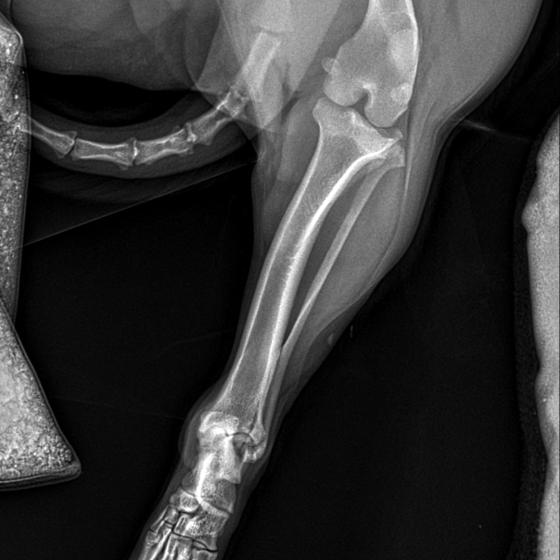

Karola nám doviezla pani, ktorá ho našla, asi jediná dobrá duša, ktorá pri ňom neprešla so zatvorenými očami. Ihneď sme s krpcom utekali na veterinu aby sa zistila závažnosť jeho zranení. Hneď pri prvých RTG snímkoch sa ukázala obojstranná fraktúra panvy, taktiež fraktúra krídla panvy a keby mu to chudákovi nestačilo, do tretice sa objavila zlomenina stavca. Karolko mal neznesiteľné bolesti, ale krásne prečkal vyšetrenie lebo vedel, že je v dobrých rukách a dostáva sa mu pomoci. Po nálezoch sme okamžite kontaktovali neurológiu a ortopédiu na veterinárnej klinike Sibra - centrum veterinárnej medicíny, kde sme dostali hneď termín na príjem.

Karol nemá žiadne neurologické deficity, po ortopedickej operácii bude vedieť behať a bez problémov bude vedieť samostatne cikať a kakať. Po tejto úžasnej správe sme samozrejme dali zelenú náročnej ortopedickej operácii pod vedením MVDr. Vatolíka. Operácia sa podarila na výbornú, Karči je "zoskrutkovaný" a vôbec nič mu nebráni v tom, aby opäť mohol behať a aktívne žiť. Momentálne sa zotavuje po operácii, musí mať prísny kľudový režim. Po vybratí stehov ho čaká hydro- a fyzioterapia, ktorá mu pomôže postaviť sa na nohy. Je to bojovník, veľmi sa chce uzdraviť a v jeho očkách je dokonale vidieť, že už kuje plány čo všetko zameškané bude musieť dobehnúť.